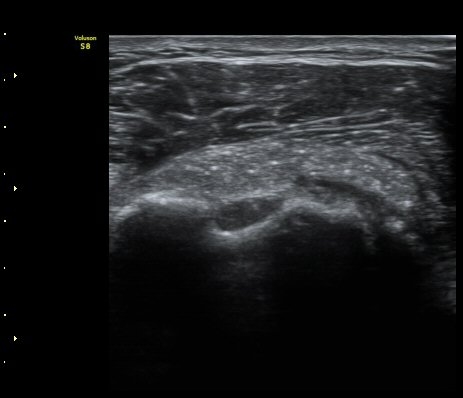

ÃÊÀ½ÆÄ °Ë»ç

À̵ιڱ٠Ⱦ´Ü¸é°Ë»ç¿¡¼­ Á¡¾×³¶³» °í¿¡ÄÚ ¼®È¸È­ À½¿µµéÀÌ °üÂûµÊ(±×¸² 1, 2, 5)

¿ÜȸÀüÀÇ Á¦ÇÑÀ¸·Î °ß°©ÇϱٰÇÀÌ ¼öÆòÀ¸·Î °üÂûµÇÁö ¸øÇϰí À̵ιڱ٠ǥÃþ¿¡

¼®È¸È­ À½¿µÀÌ °üÂûµÊ(±×¸² 3)

À̵ιڱ٠Á¾´Ü¸é°Ë»ç¿¡¼­µµ Á¡¾×³¶³» ¼®È­È­ À½¿µÀÌ °üÂûµÊ(±×¸² 4).